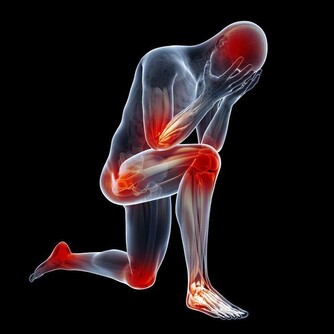

首先會感到尿頻,患者會發現自己的排尿頻率比之前要高,最明顯的就是會不停地起夜,休息不好。

其次,患者很難將尿液排出體外,或是排尿持續時間過長,排尿後感覺仍有部分尿液未被排出。

再次,患者有可能在還沒到衛生間時,尿液便開始滴漏,或是在上完廁所後繼續滴尿。

此外還會部分患者會有一些不太常見的症狀,

例如尿痛、射精時感到下體疼痛、尿液或精液中參有血跡、無法正常勃起等。